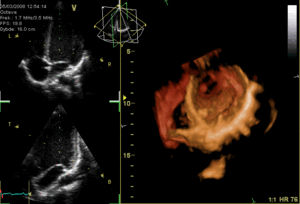

- Echocardiography ("echo")

- Ultrasonography of the heart to inspect chambers, valves, and blood flow. Often utilizes the Doppler effect to determine blood flow through valves (stenosis & regurgitation) and through the septum (ASD & VSD). Agitated saline can be used as contrast for blood flow and microbubbles for capillary blood flow contrast.

- Transthoracic echocardiogram (TTE)

- Echocardiogram of the heart through the thorax external to the body. Much easier to perform than TEE because it is non-invasive and takes less time, but has several disadvantages (namely clarity of images).

- Transesophageal echocardiogram (TEE)

- Echocardiogram of the heart through the esophagus. TEE can require sedation or general anesthesia and the patient must be NPO.